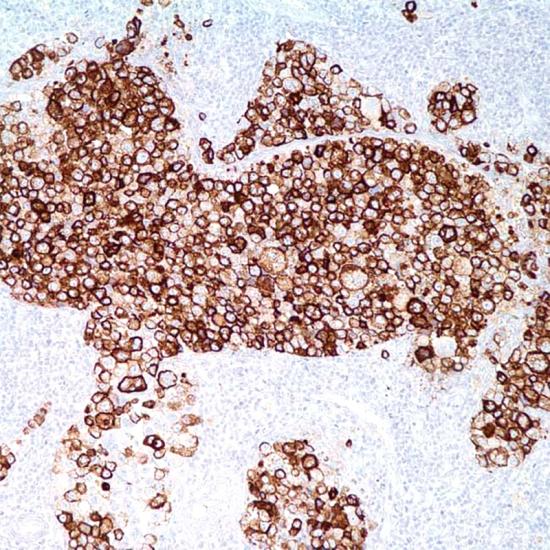

Mesothelioma

MC抗體試劑(免疫組織化學(xué)) 閩廈械備20180072號(hào)

• 陽(yáng)性部位:

細(xì)胞漿/細(xì)胞膜

• 陽(yáng)性對(duì)照:

間皮瘤

HBME-1

Mesothelioma在正常、增生的間皮和間皮瘤均有表達(dá),在上皮型、混合型間皮瘤的上皮樣成分陽(yáng)性,梭形細(xì)胞間皮瘤呈陰性反應(yīng)??寺√?hào)HBME-1標(biāo)記甲狀腺乳頭狀癌和濾泡狀癌,但在正常的甲狀腺不表達(dá),因此可用來(lái)鑒別甲狀腺的良惡性病變。MC對(duì)間皮瘤(陽(yáng)性率較高)和腺癌(陽(yáng)性率較低)的鑒別也有一定意義。